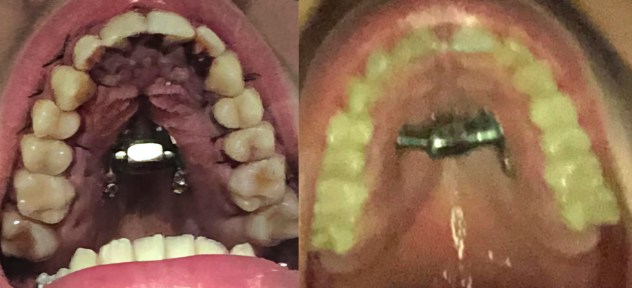

100% true, and I am just now noticing it. I have very little fat under my eyes, there will be no way to bypass saddle infra implants.Lateral projection is not undereye support. Be prepared for a wider nose.

I am not noticing much of a change in the nose to be honest. But even if it gets substantially wider, I am ok with that. Fixing soft tissue will be the last of my looksmaxing steps.